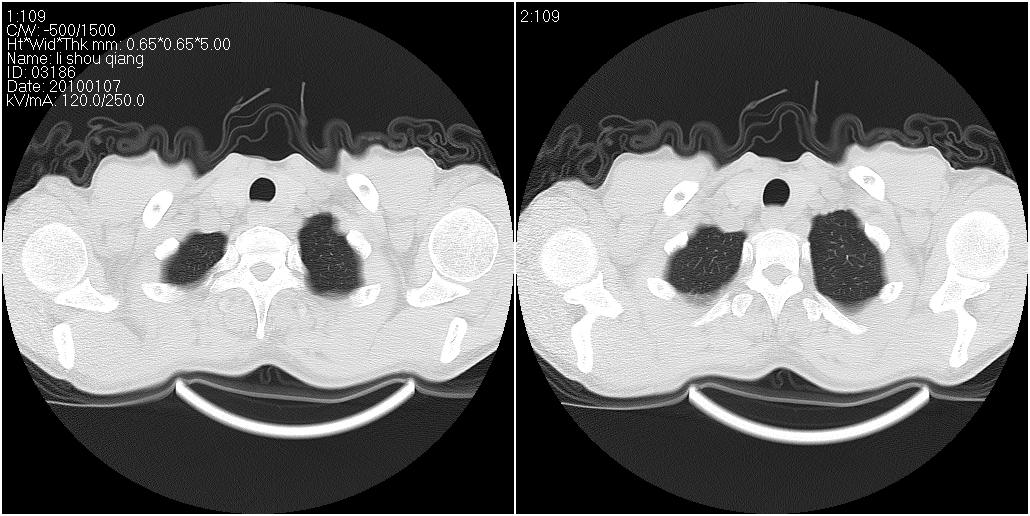

右肺中叶外侧段见一不规则的软组织肿块,边缘可见毛刺,并见厚壁空洞,与胸膜分界欠清。另左下肺见多个小囊状扩张区